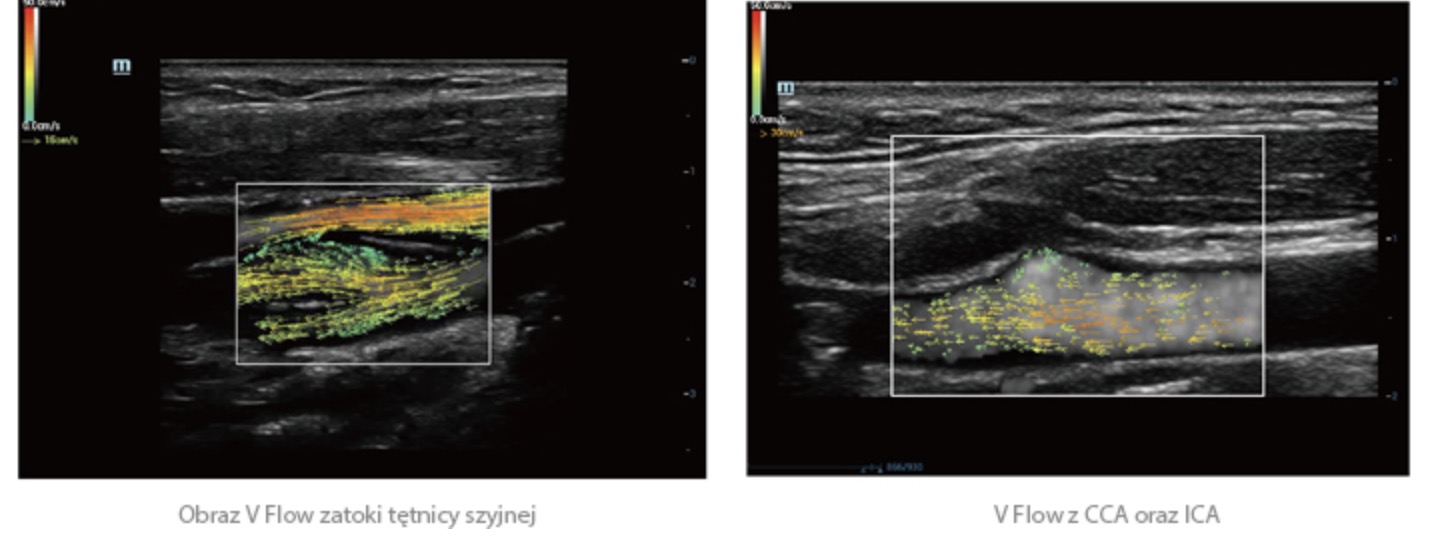

Oprócz uzyskiwania jako?ci obrazu typowego dla aparatów klasy premium, Resona 7 rozszerza mo?liwo?ci klinicznych badań USG dzi?ki rewolucyjnej funkcji V Flow, s?u??cej do oceny hemodynamiki naczyń, a tak?e najlepszej na rynku funkcji inteligentnego, automatycznego uzyskiwania p?aszczyzny na podstawie zestawów danych obj?to?ciowych 3D, umo?liwiaj?cej diagnozowanie stanu Centralnego Uk?adu Nerwowego u p?odu. Aparat Resona 7 ??czy w sobie najbardziej intuicyjn?, wielodotykow? obs?ug? za pomoc? gestów oraz wszystkie kluczowe funkcje kliniczne, co sprawia i? jest prawdziwym liderem we wprowadzaniu innowacji w ultrasonografii.